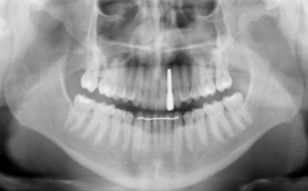

Debido a la agenesia congénita del incisivo lateral superior izquierdo, el paciente fue tratado 12 años atrás mediante ortodoncia convencional para cerrar el diastema (Figuras 1 y 2).

Finalizado el tratamiento con ortodoncia (Figuras 3, 4 y 5), y una vez que el paciente optó por la opción del implante; se repitió el escaneado intraoral y se obtuvo un escáner de haz cónico para la correcta planificación de la cirugía implantológica (Figura 6).